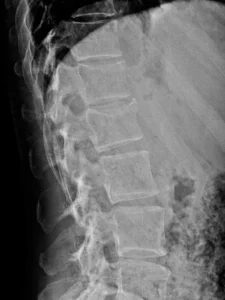

Radiología

Radiografías AP y lateral de columna lumbar, incluye los segmentos dorsales distales. Fractura con reducción de la altura, a predominio anterior, de los cuerpos de D12 y L1, mejor visualizada en la proyección lateral. Irregularidad del ángulo anterosuperior en ambos niveles y probable protrusión del muro posterior de L1 hacia el canal.

Hallazgos principales en Rx:

- En la proyección lateral se identifica pérdida de altura del cuerpo vertebral de D12 y L1, predominante anterior, compatible con fractura por compresión.

- Puede determinar discreta cifosis segmentaria en la unión toracolumbar.

- Alteración del muro posterior o trazo vertical sugerente de fractura más compleja (dato que suele requerir TC).

Comentario didáctico: La Rx puede detectar la fractura y orientar el nivel, pero subestima con frecuencia el compromiso del muro posterior, el canal y los elementos posteriores.